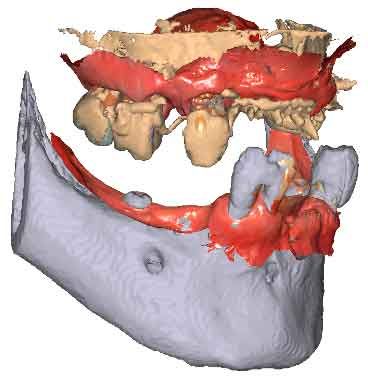

When traditional IOS scans lack necessary references, Cone Beam Computed Tomography (CBCT) data serves as a possible alternative. By utilizing CBCT scans, clinicians can establish accurate reference positions for treatment planning.

To be able to use CBCT data as initial models, we need to transform the DICOM file into an STL file.

By importing patient DICOM files instead of the IOS scans, clinicians can register jaw motion, facilitating precise treatment planning.

Import the segmented and converted CBCT models as initial models in TWIM

Select 4 virtual points on the mandible of the imported bone mesh